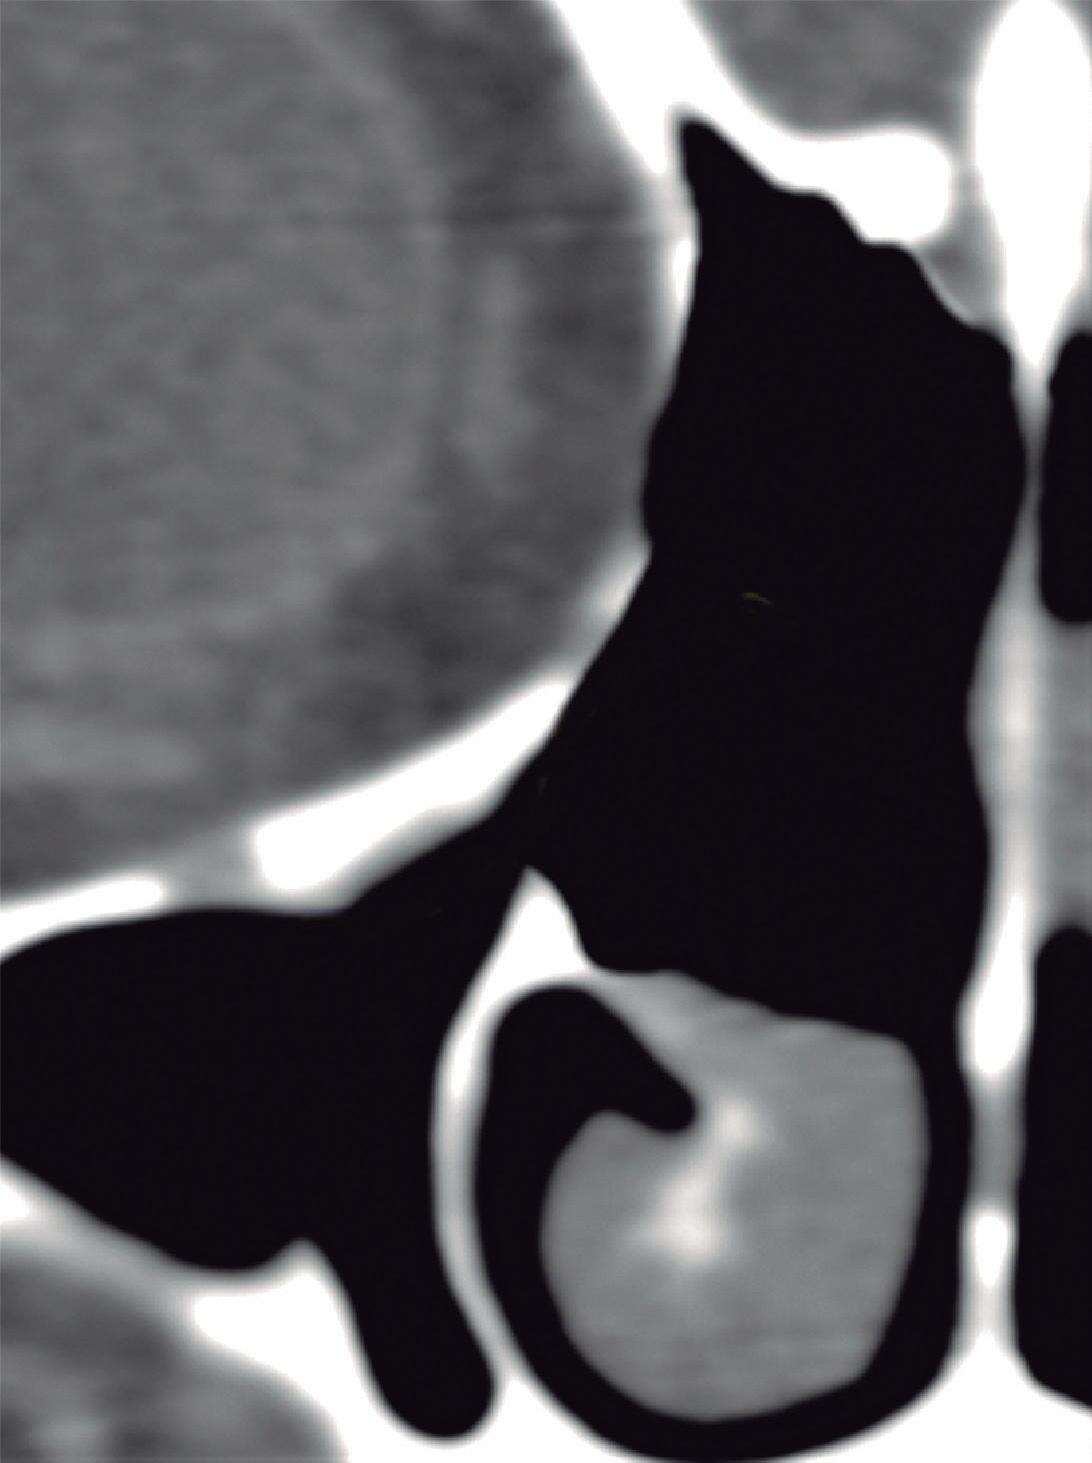

1-4. TC e reconstrução 3D com destaque para estrutura etmoidal (em vermelho), funcionando como câmaras de baixa pressão para drenagem do seio maxilar.

1-7. TC com reconstrução 3D mostrando em vermelho apenas o seio etmoidal e não o osso etmoidal, e sua relação com a fossa nasal, o seio maxilar, órbita e fossa anterior.

Este complexo anatômico chamado seio etmoidal, controla a pressão e o fluxo aéreo que penetra nos verdadeiros seios paranasais e pode ser interpretado como um sistema de câmaras aerodinâmicas de baixa pressão cuja topografia particular faz dele o centro anatomofuncional do aparelho rinossinusal.